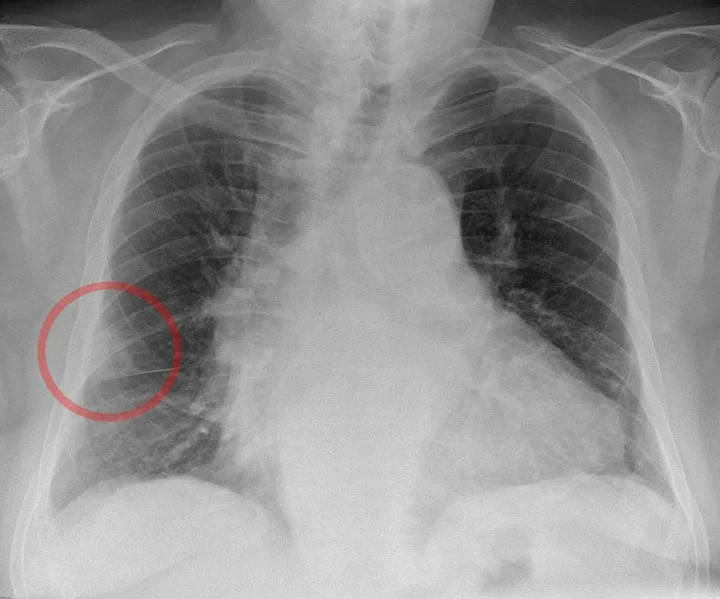

A chest X-ray shows a Hampton hump. What caused this finding, and why is this complication less likely to occur?

What is pulmonary infarction - pulmonary embolism obstructed pulmonary arterial blood flow

-Less common because bronchial circulation may protect against infarction.